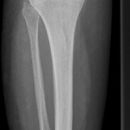

Unterschenkel lateral (medio-lateral, 2. Ebene)

Deckungsgleiche Darstellung der Femurkondylen. Distaler Unterschenkel mit seitlicher Projektion des Sprunggelenkes. Die Fibula projiziert sich in Höhe des Sprunggelenks auf das mittlere bis hintere Drittel der Tibia.